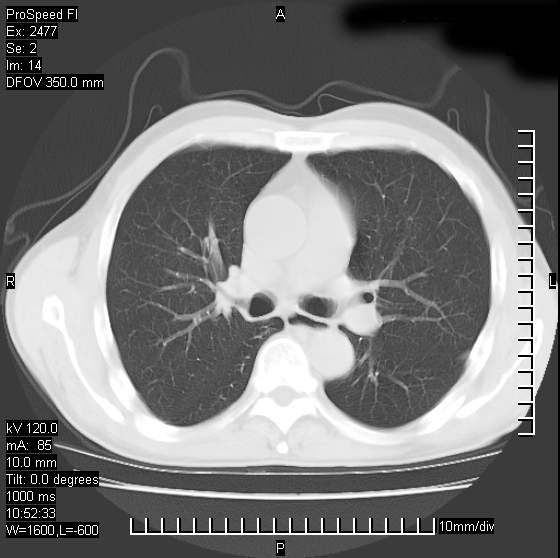

以下是引用天南地北在2007-10-9 14:29:00的发言:[br]1:右上肺结核[br]2:右肺下叶肿块:不支持肺癌,首先考虑炎性病变-肺脓疡可能性大[br]理由:1:临床病史支持,肺脓肿症状不明显应该是不规则服药造成。[br] 2:肿块边缘模糊,周围可见炎性渗出,长毛刺,内见支气管征,不过有点不规则。[br] 我感觉下肺癌这个诊断有点偏左,建议积极抗炎治疗后复查

以下是引用卜一在2007-10-9 15:55:00的发言:[br][br] [br] 1:右上肺结核[br]2:右肺下叶肿块:不支持肺癌,首先考虑炎性病变-肺脓疡可能性大[br]理由:1:临床病史支持,肺脓肿症状不明显应该是不规则服药造成。[br] 2:肿块边缘模糊,周围可见炎性渗出,长毛刺,内见空气支气管征,不过有点不规则。[br] 我感觉下肺癌这个诊断有点偏左,建议积极抗炎治疗后复查![br]支持! [br] [br] [br]

以下是引用wxy7406在2007-10-9 21:02:00的发言:[br]结合临床病史首先考虑感染性病变,但周围型肺癌不能除外,1.患者年龄偏大2.临床有咯血3.(也觉得是最重要的一点)病灶内有偏心性空洞。

以下是引用王仕学在2007-10-9 13:48:00的发言:[br]右下肺周围性肺癌可能性大,最好活检吧

以下是引用hhcckk在2007-10-9 15:18:00的发言:[br]右上肺病灶考虑结核,病灶多种形态并存(纤维化、增殖性病灶并存)[br]右下肺病灶比较难说,个人意见更趋向于“天南地北”的诊断----肺脓肿[br]1、病人有明显的寒战,高热,肿瘤病人很少出现[br]2、病灶周围的肺纹理走向柔和,没有肿瘤病灶常见的集束征[br]3、病灶边缘的毛刺较长,恶性肿瘤多为短毛刺[br]痰中血丝和病人的年龄是两个不利于良性肿块的因素,建议早点活检

以下是引用ydx_74在2007-10-9 15:53:00的发言:[br]右上肺结核,右下中心性肺癌可能大,肺门淋巴结肿大。